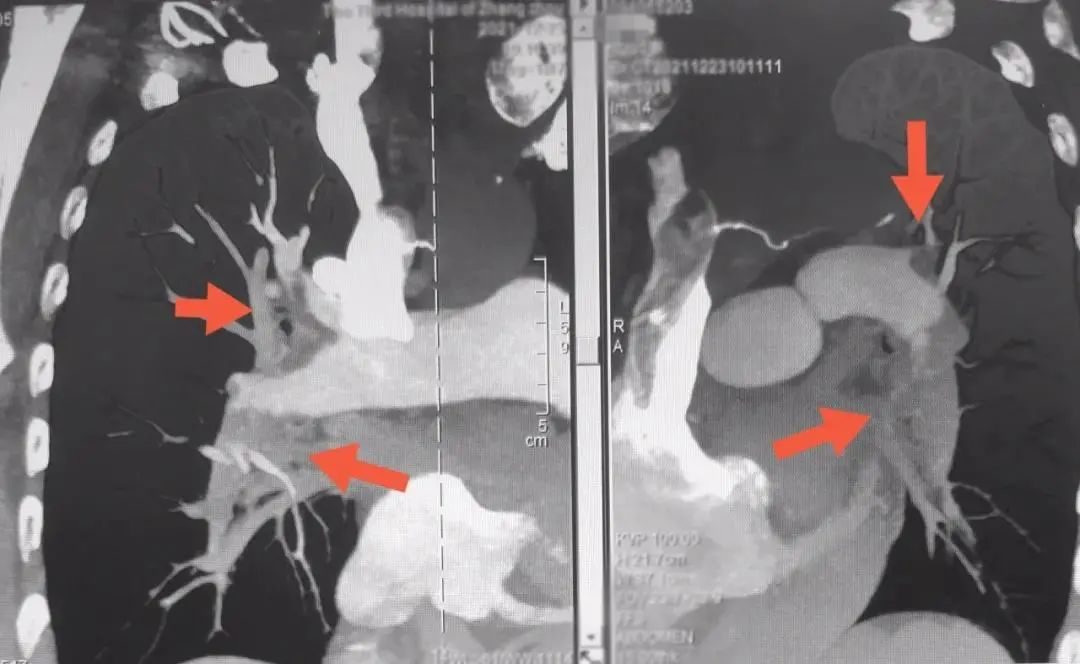

进一步CT检查显示患者肺部大面积血管堵塞,随时危及患者生命,单纯的保守治疗效果不好,死亡率极高。

术前肺动脉主干多发栓塞

术后肺动脉血栓完全消失